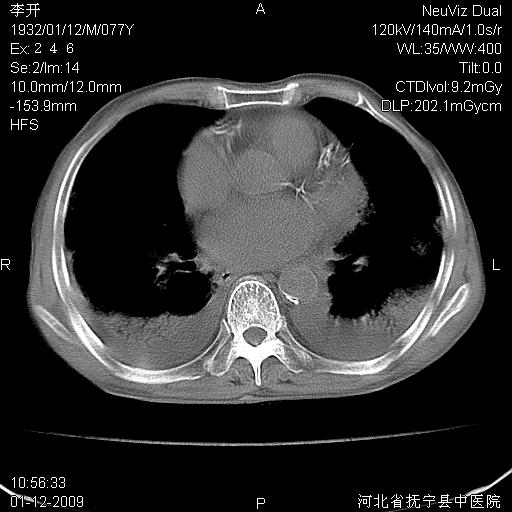

以下是引用黑白光影在2009-1-19 16:49:00的发言:[br]心衰肺水肿;心包、胸腔积液;冠脉钙化;肺部感染。